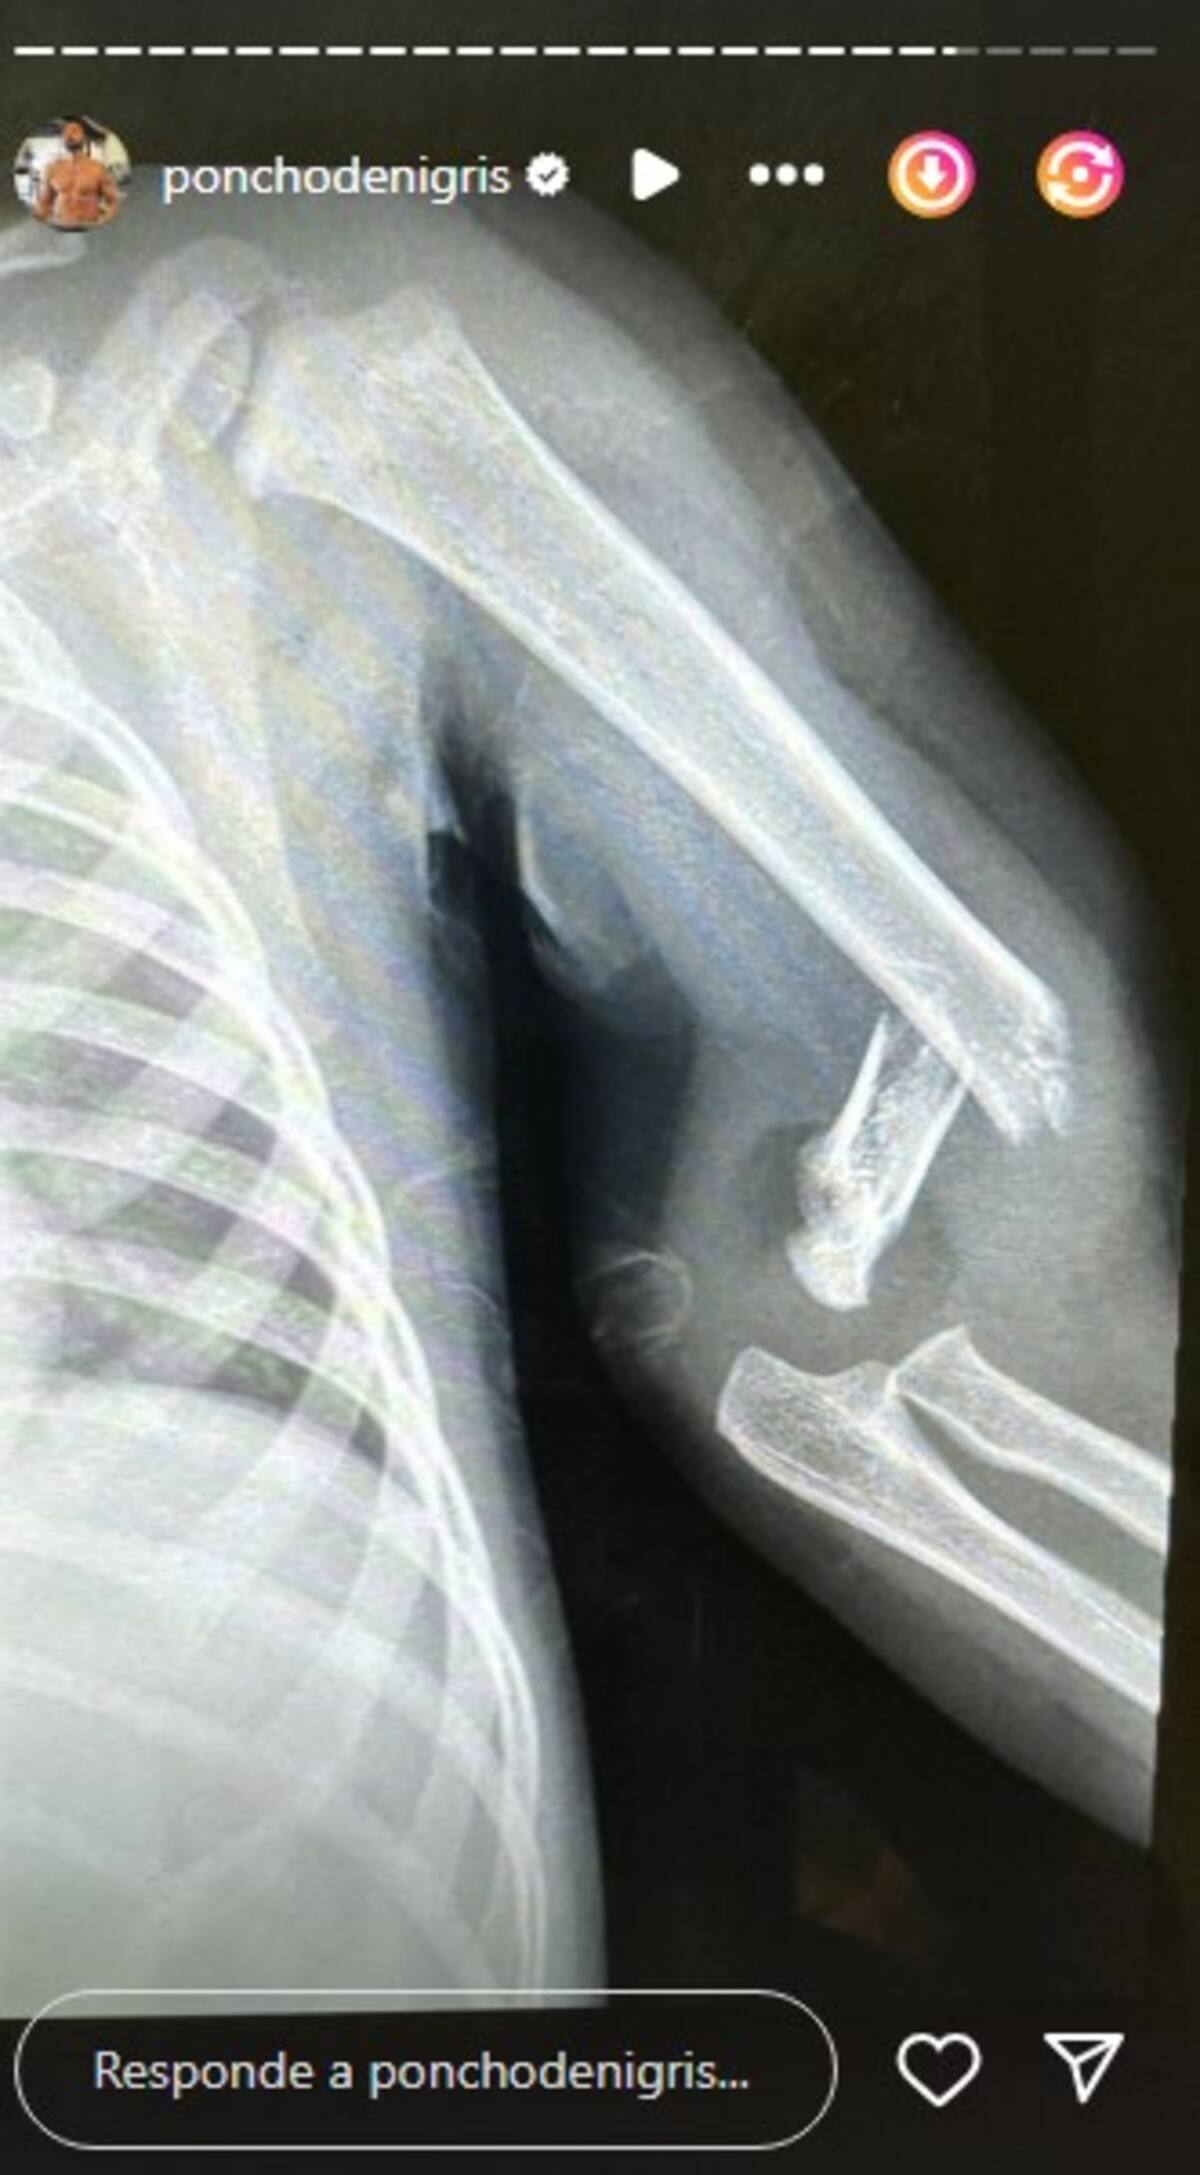

El ex participante de ‘La Casa de los Famosos México’ contó en sus redes sociales una radiografía donde se evidencia la fractura ósea que afectó a Toñito. Posteriormente, a través de sus historias de Instagram, informó que su hijo tuvo que ser sometido a una operación para arreglar el brazo del pequeño.

Poncho de Nigris y su esposa, Marcela Mistral, utilizaron sus redes sociales recientemente para informar a sus seguidores sobre el estado de salud de su hijo menor, Toñito, quien sufrió una fractura en el brazo. El incidente ocurrió el miércoles 10 de julio, y según explicó el propio Poncho de Nigris, decidieron compartir la situación para evitar malentendidos.

Poncho contó que fue un accidente que le pasaría a cualquier niño, ya que se encontraba en el exterior jugando con sus hijos, Ponchito, el mayor estaba en la bicicleta, él estaba en el scooter con su hija y en un descuido Toñito se cayó resultando en una fractura de brazo por lo que rápidamente se trasladaron al hospital para que recibiera atención.